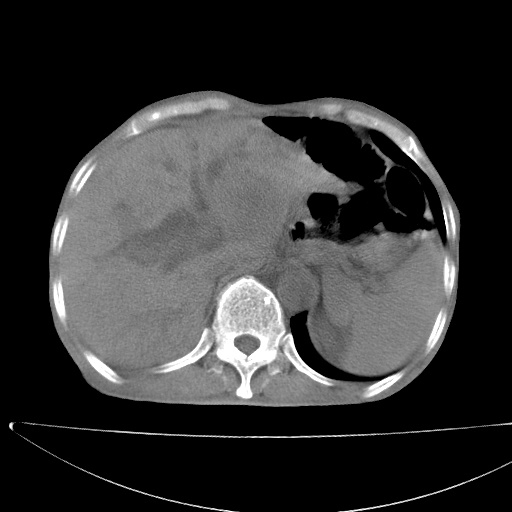

标题: CT17147:男70岁,上腹部不适1月。 [打印本页]

患者男70岁,上腹部不适1月。8年前有胃癌手术史。余病史不祥。

考虑胃癌复发并小网膜淋巴结转移侵及肝脏胆总管梗阻

考虑胃癌复发并腹腔内淋巴结转移。

1)胃癌术后,复发不排除。

2)肝脏转移瘤。

3)肝脏钙化灶。

4)胆囊增大。

5)腹膜后多发性淋巴结转移。

6)腹水。

7)右侧少量胸水。

建议:增强扫描。

1)胃癌术后,不排除复发可能。2)考虑肝脏及腹膜后淋巴结转移瘤。3)肝内胆管扩张,胆囊增大。4)肝内胆管结石(或钙化)。5)脾脏钙化灶。6)腹水。7)右侧少量胸腔积液。

建议:行ct增强扫描检查。

1、胃癌根治胃空肠吻合术后,残胃癌?

2、肝门区占位性病变并胆道上段梗阻(肝内胆管扩张、胆囊增大),考虑肝门区淋巴结转移累及胆总管,建议ct增强扫描;

3、右侧胸腔少量积液、少量腹水;

4、肝右叶胆管结石。